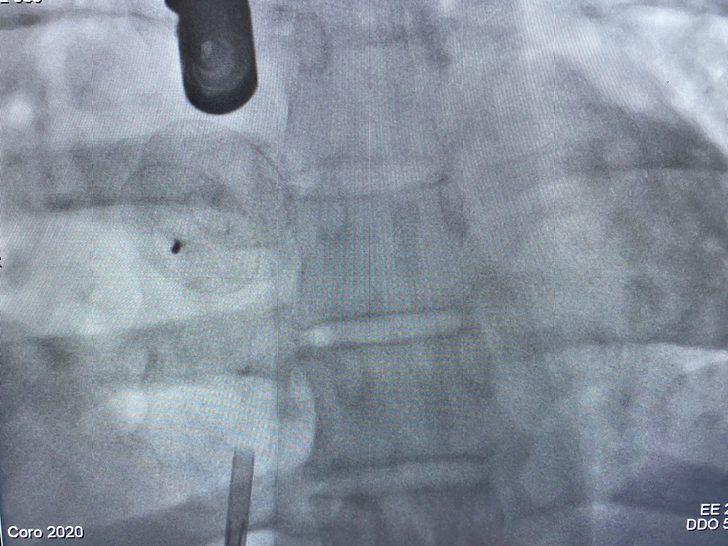

Prof. Dr. Zülkif Karahan, Doç. Dr. Hakan Akelma ile uzman doktorlar Raşit Tanircan ve Fetullah Kayhan'ın da bulunduğu ekip tarafından gerçekleştirilen anjiyografi yöntemiyle hasta tedavi edildi.

Uzm. Dr. Fetullah Kayhan, tetkiklerde hastanın kalbinde 2,3 santimetrelik delik tespit ettiklerini anlatarak, yaptıkları kapalı yöntemle operasyonun hasta için oldukça konforlu olduğunu belirtti.

Uzm. Dr. Raşit Tanircan da operasyonun hazırlık işlemleri de dahil yarım saat sürdüğünü, hastanede artık bu tür yöntemleri başarıyla uyguladıklarını söyledi.